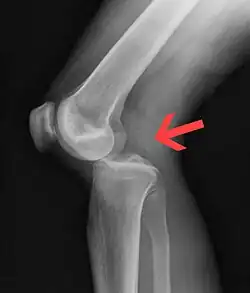

![]() | |

| Plain lateral X-ray of the left knee showing a posterior knee dislocation[1] | |

Plain X-rays, CT scan, ultrasonography, or MRI may help with the diagnosis.[2][11] Findings on X-ray that may be useful among those who have already reduced include a variable joint space, subluxation of the joint, or a Segond fracture.[5]